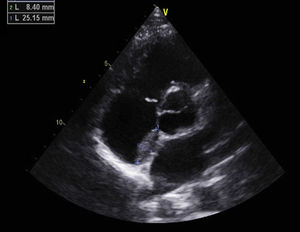

Antiphospholipid syndrome (APS) is an autoimmune disease, with antiphospholipid antibodies associated with hypercoagulability, vascular thrombosis, and fetal loss.1,2 Cardiac involvement occurs frequently, and is deeply related to hypercoagulability in spite of recommended anticoagulant therapy.3 In this report, we describe the images of a Caucasian 19-year-old male, with a previous history, 4 years earlier, of an acute in situ right chamber thromboembolic episode submitted to a surgical intracardiac thrombectomy. At this time APS was diagnosed with increased levels of lupus anticoagulant and IgM anti-beta(2)-glycoprotein I. All other autoantibodies were negative. He was readmitted in April 2012 with an initial suspicion of endocarditis. Intracardiac and inferior vena cava thrombi as well as acute and chronic pulmonary thromboembolism were detected in spite of adequate anticoagulation. After full dose anticoagulation he improved well and was discharged. In September 2012 he was readmitted after 2 weeks of fever, dyspnea and left thoracic pain again with pulmonary thromboembolism. Transthoracic echocardiogram (TTE) revealed an image suggestive of a thrombus at the upper part of the atrial septum in the right atrium (25×8mm), Image 1, and in the inferior vena cava (18mm) near the roof of the right atrium, Image 2. Also in the infundibulum of the right ventricle and in the right ventricular outflow tract several freely moving masses were visualized, indicative of thrombus near the lateral wall, Image 3. A long course of antibiotic was done and all microbiological tests proved negative. Hydroxychloroquine and colchicine were added to an intensive antithrombotic regimen of acenocumarol, enoxaparin and acetylsalicylic acid with a significant reduction of the right atrium and inferior vena cava thrombi and a complete disappearance of the right ventricular masses. The patient improved clinically and no further relapses were observed during follow-up.